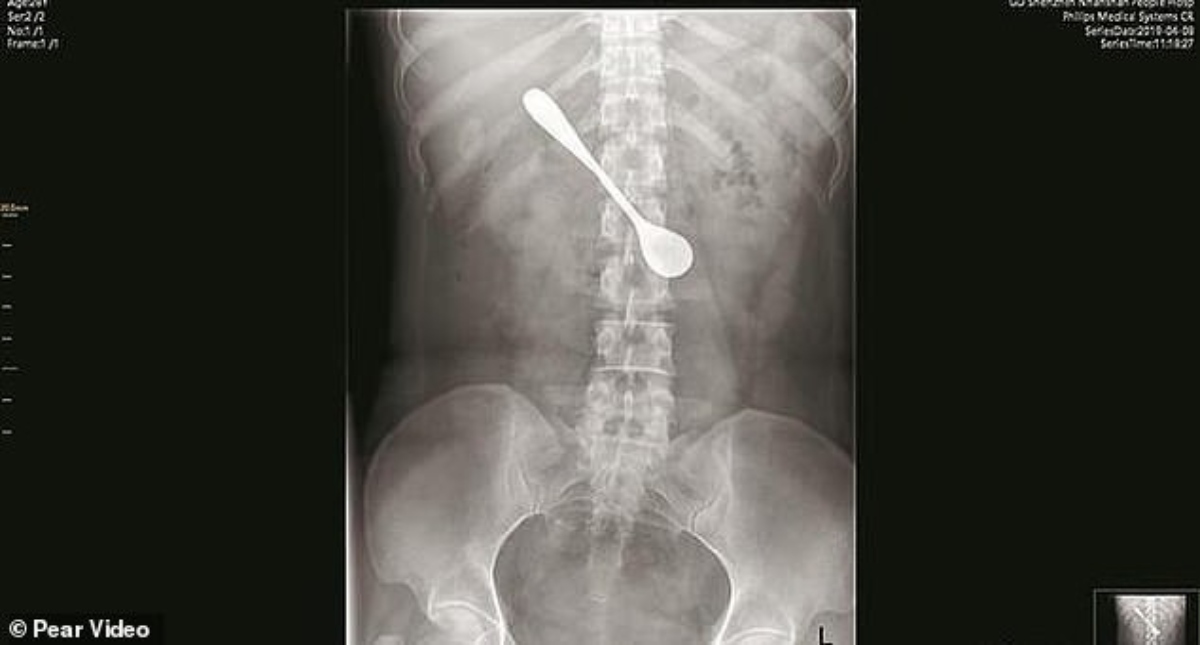

La mujer decidió no visitar al médico inmediatamente después del hecho para no perderse la celebración de un festival Leer más